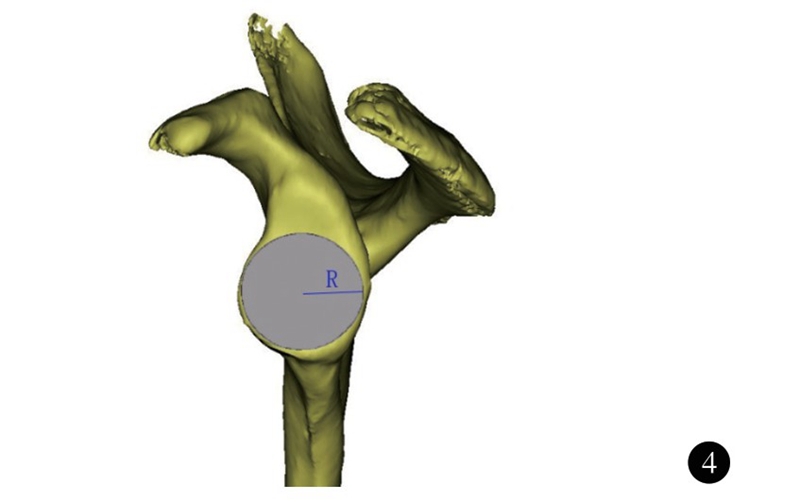

肩胛盂近似梨形,下半部分较上半部分大。在反式肩关节置换术中,肩胛盂侧假体安装在肩胛盂下部,因而肩胛盂下半部分的大小决定了假体的大小。韩国Ji等测量了本国肩胛盂下部的解剖学参数,其中肩胛盂下部半径男女分别为(17.1±2.1) mm和(15.4±1.6)mm,性别之间差异有统计学意义。

图4 肩胛盂下半部分半径(R) 示意图